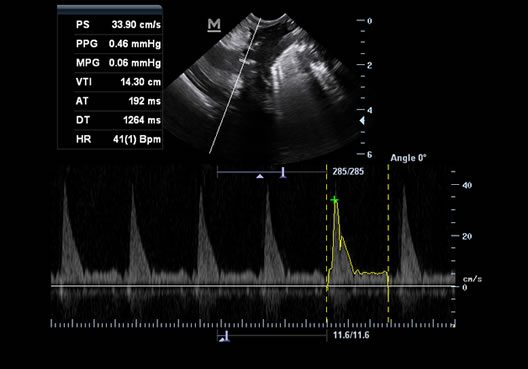

Аппарат среднего класса с цветным допплером для обследования животных: от мелких домашних до крупных сельскохозяйственных животных. Диагностическая система имеет компактные размеры, небольшой вес и сумку для переноски, которая обеспечивают удобства для транспортировки. Прибор может работать одновременно с тремя датчиками. Mindray Z60 Vet автоматически распознает структуры анатомических областей, увеличивает контрастность их краев и контуров. Аппарат многофункционален, производителен и обладает отличной глубиной визуализации.

Режимы сканирования B/M/Color Dopler/Color M/Power/Directional Power Doppler Flow Imaging

Поддержка тканевого доплера (TDI) Да

Двойной дисплей B/C, B/TDI, B/M, B/PW да